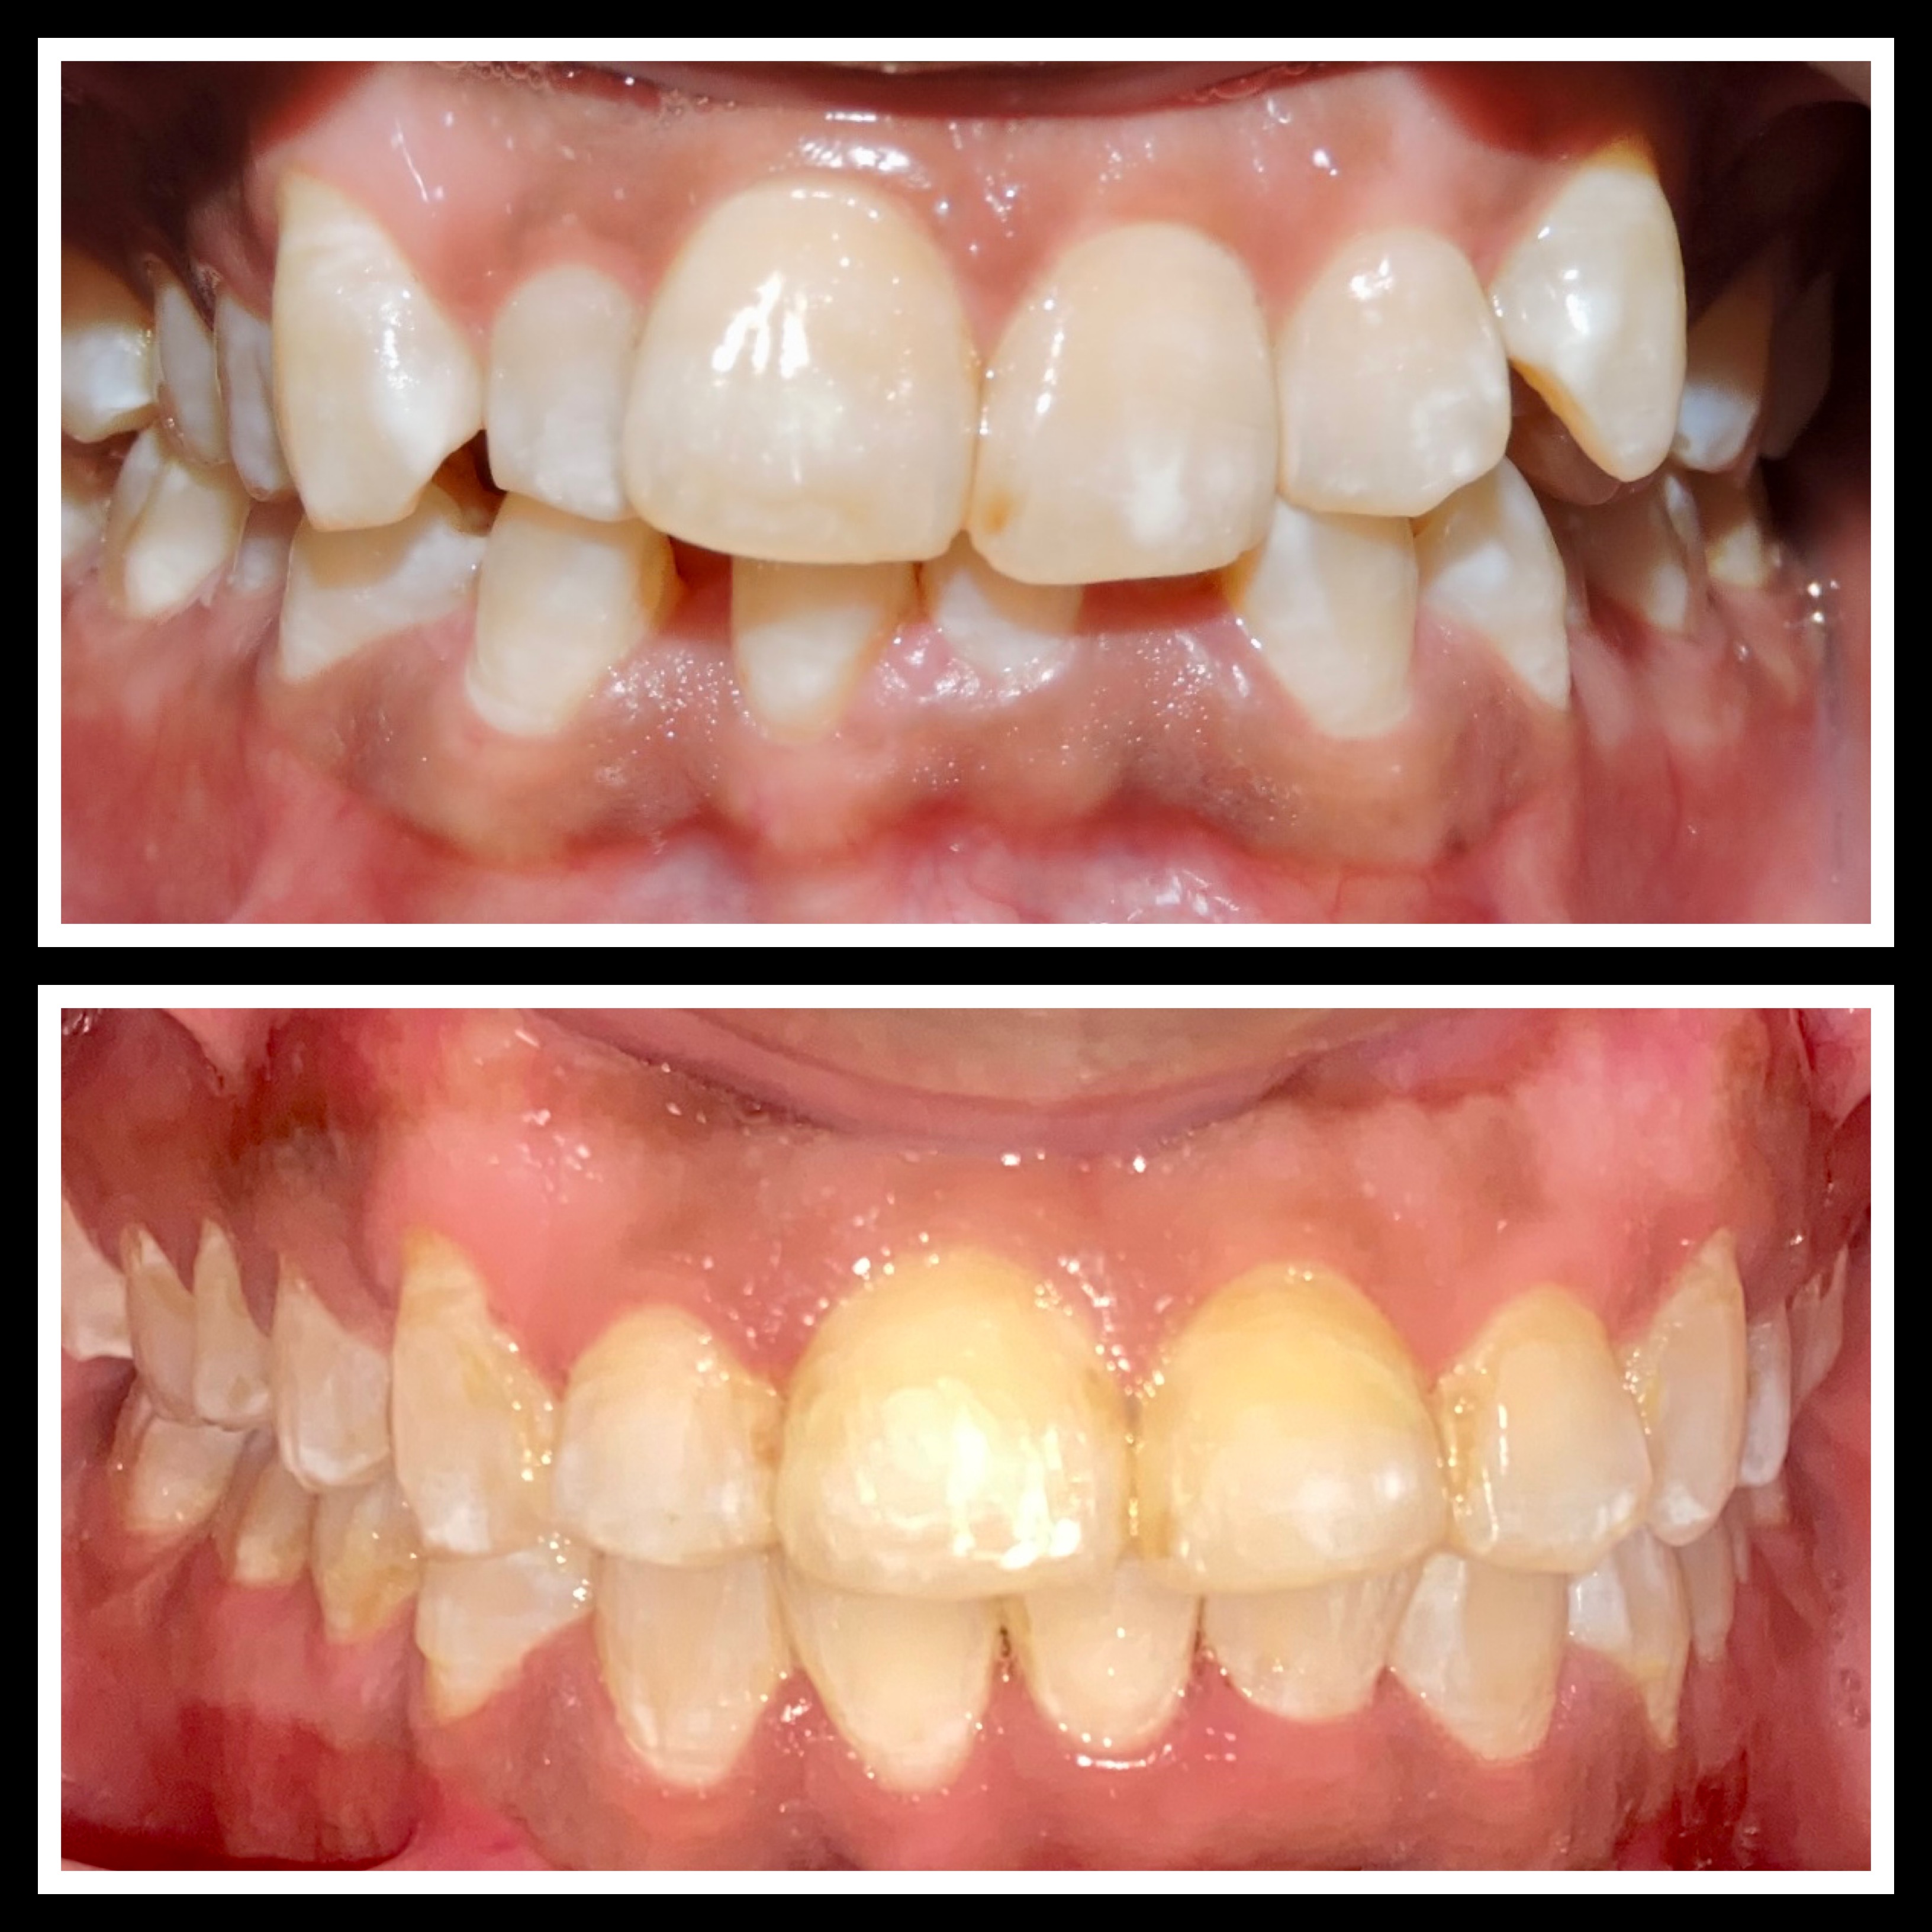

Gallery